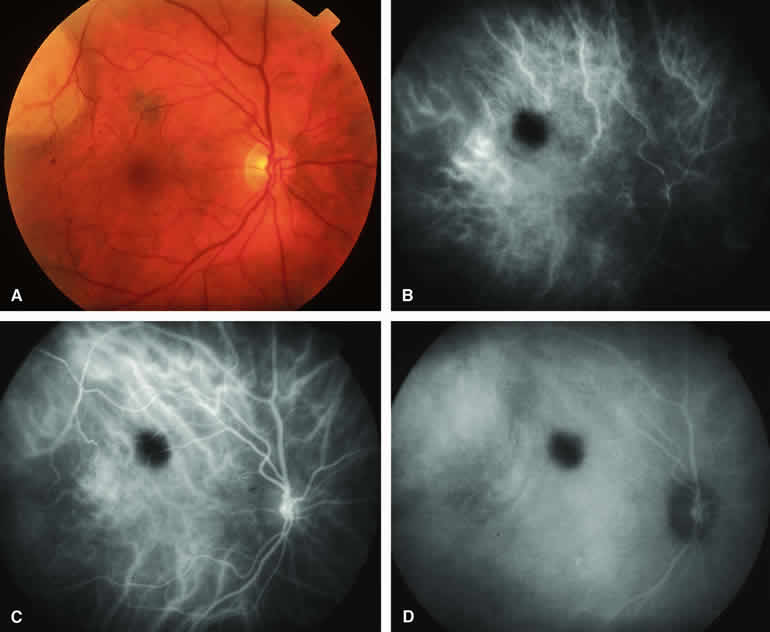

ICG angiography of a typical melanotic choroidal nevus (see Fig. 2) shows better definition of the basal area of the lesion than does fluorescein angiography. The entire lesion appears completely and uniformly dark throughout the ICG angiogram. Only the larger retinal blood vessels overlying the nevus are usually demonstrated on ICG angiography.